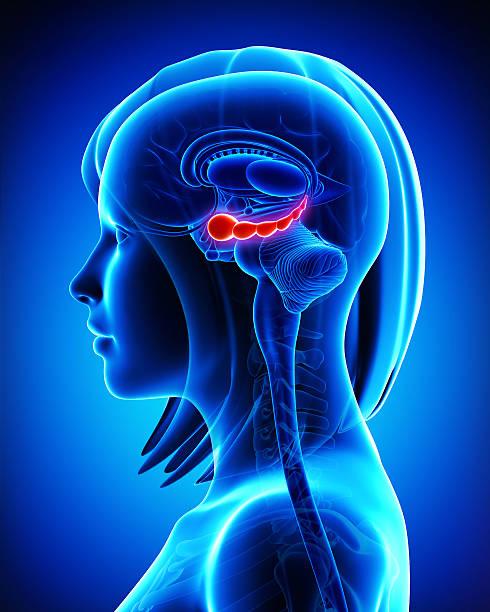

Die Inhaltsstoffe von BrainChain wurden sorgfältig ausgewählt, um das allgemeine Wohlbefinden und die Zellgesundheit auf natürliche Weise zu unterstützen. Dabei spielen mehrere Gehirnareale und Systeme eine zentrale Rolle:

Dieser Bereich ist maßgeblich an Denkprozessen, Planungen und Entscheidungsfindungen beteiligt. Nicotinamid-Ribosid (NR), eine Vorstufe des zellulären Coenzyms NAD+, unterstützt den Zellstoffwechsel und trägt so zur normalen Funktion von Gehirnzellen bei.

Ein entscheidender Bereich für Lernprozesse und Gedächtnisbildung. Löwenmähne (Hericium erinaceus) wird traditionell für die Unterstützung der allgemeinen neuronalen Gesundheit verwendet und trägt zur normalen Funktion des Nervensystems bei.

Diese Bereiche regulieren Emotionen und Stressantworten. Eine ausgewogene Darmflora, unterstützt durch Inulin, kann über die Darm-Hirn-Achse indirekt zu einem normalen emotionalen Gleichgewicht beitragen. Zusätzlich helfen antioxidative Substanzen wie Resveratrol und Quercetin, die Zellen vor oxidativem Stress zu schützen.

Essentiell für Koordination und motorische Fähigkeiten. Die in BrainChain enthaltenen Inhaltsstoffe, wie Resveratrol und NR, unterstützen den Zellstoffwechsel und tragen zur normalen Zellfunktion und zum Schutz vor oxidativem Stress bei.